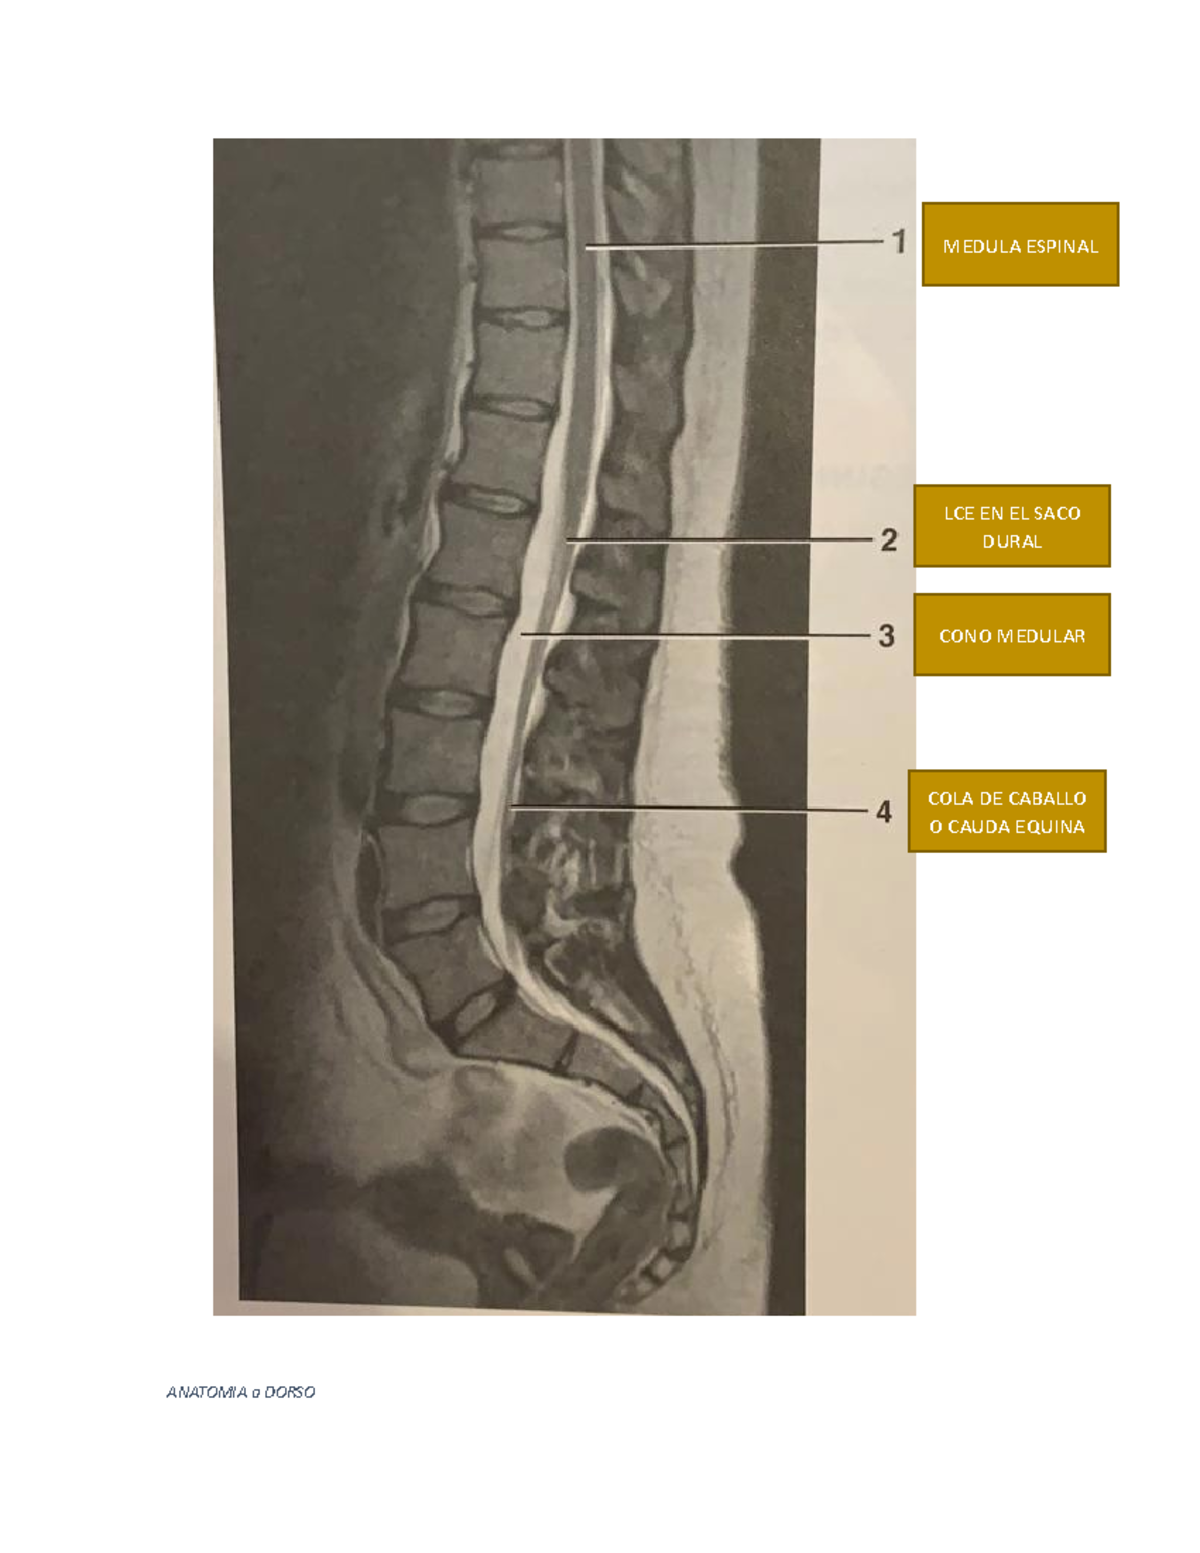

Anatomia a Dorso ANATOMIA a DORSO LCE EN EL SACO DURAL CONO MEDULAR COLA DE CABALLO O CAUDA

O que é compressão sobre o saco dural? A SCM se caracteriza pela compressão do saco dural e seu conteúdo - medula espinhal e/ou cauda equina - por massa tumoral extradural. Entretanto, pode ocorrer por tumoração primária ou secundária, mas, quando se trata da metástase, ocorre principalmente nos corpos vertebrais, onde há maior vascularização. O […]